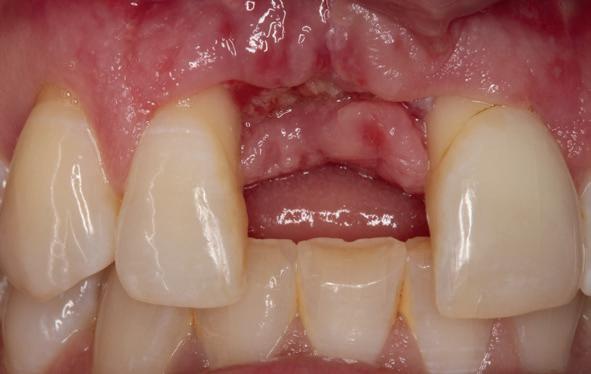

Implantologische behandelingen in het esthetische front vragen meer dan technische vaardigheid alleen. Ze vragen om overzicht, timing, vertrouwen en een team dat als vanzelf samenwerkt onder druk. Juist bij complexe casussen, waarin angst, infectie en hoge esthetische verwachtingen samenkomen, wordt zichtbaar hoe bepalend de rol van de tandartsassistent is.

Deze casus beschrijft een uitgebreide immediate implantaatbehandeling bij een patiënt die door meerdere collega’s werd geweigerd. Niet omdat de mogelijkheden ontbraken, maar omdat de complexiteit vroeg om een perfect afgestemde samenwerking. Het verhaal laat zien hoe de assistent in zo’n traject veel meer is dan een uitvoerende kracht of “mal”, maar een dynamische surgical guide die het proces mede stuurt, bewaakt en mogelijk maakt.De patiënt: wanneer alles samenkomt

Ze kwam binnen op een dinsdagochtend, iets voor achten. Een vrouw van begin zeventig, met een zachte stem en ogen die meer vertelden dan haar woorden. Ze vertelde dat ze een eigen B&B had en dat ze zich nauwelijks kon voorstellen gasten te ontvangen zonder tanden. Op dit moment kon ze echter nauwelijks lachen. “Het doet pijn… en het ruikt soms ook niet goed,” zei ze bijna verontschuldigend. Haar oude bovenbrug, die ze al meer dan twintig jaar droeg, was langzaam maar zeker ingestort. Er was sprake van cariës onder meerdere pijlers, pusafvloed,

chronische ontsteking en een brug die mobiel was en elke beet pijnlijk maakte. Ze had inmiddels meerdere tandartsen bezocht. Drie hadden haar geweigerd. Te complex. Te veel wensen. Te onvoorspelbaar.

De kern van haar vraag was eenvoudig en tegelijkertijd uitdagend: Is het mogelijk om mijn huidige brug te dupliceren en een nieuwe brug te vervaardigen met minder complicaties?